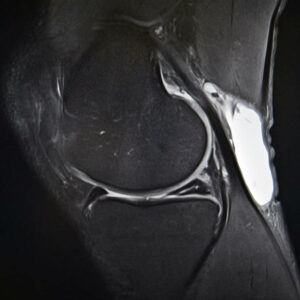

5 Essential Tips For Meniscal Tear Treatment

Ask any professional athlete and they will tell you a torn meniscus is one of the most common knee injuries. That’s because any activity – sports-related or otherwise – that causes you to forcefully twist or rotate your knee, can result in a torn meniscus. The meniscus is the C-shaped piece of [Read More]